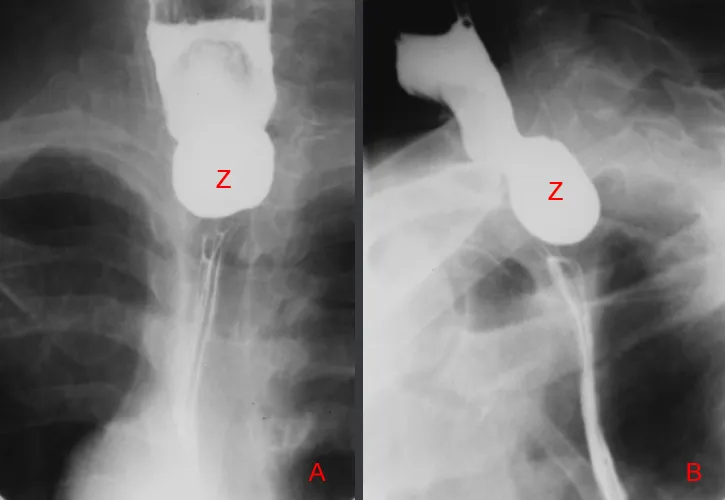

- Zenker's Diverticulum:

- Pulsion diverticulum (Killian's dehiscence).

- Regurgitation (undigested food), halitosis, gurgling.

⭐ Zenker's diverticulum is a pulsion diverticulum in Killian's dehiscence, presenting with regurgitation of undigested food and halitosis.